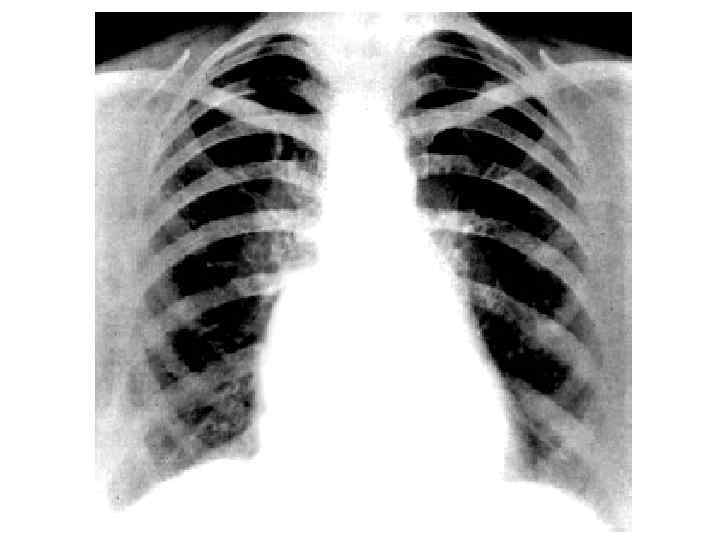

Течение митрального стеноза I стадия — одышки нет в покое и при нагрузке, больные полностью компенсированы. II стади я — при знаки нарушения кровообращения в малом круге, выявляющиеся только при физической нагрузке. III стадия — в малом круге выраженные признаки нарушения кровообращения; в большом круге — начальные признаки застоя. IV стадия — выраженные признаки застоя в малом и большом кругах кровообращения. V стадия — дистрофическая.